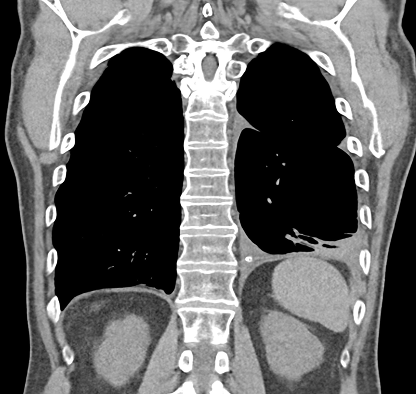

In a study patient, fluid occupying nearly half of the hemithorax at baseline was significantly reduced by 30 days and remained low at 60 days, demonstrating consistent drainage and lung re-expansion over time.

CT Baseline

30 Days

60 Days